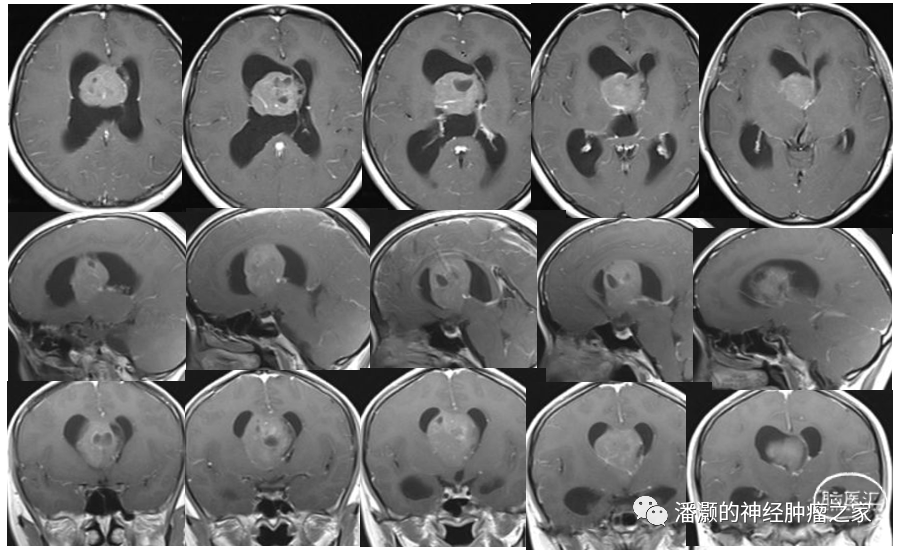

术后第三天复查头颅MR如下:

复查MRI提示两部位肿瘤均切除满意。未见明显肿瘤残留。

术后病理结果提示中枢神经细胞瘤,予以出院,出院后行放疗进一步治疗。